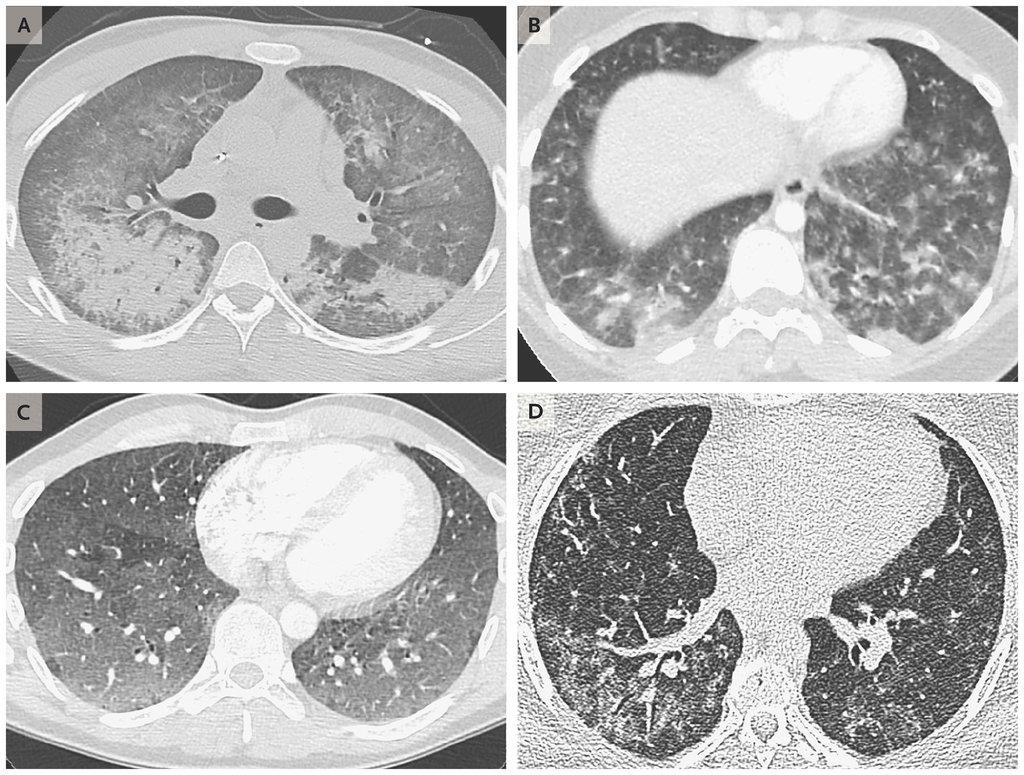

| Hình ảnh scan phổi của 4 bệnh nhân tuổi từ 19 đến 49, cho thấy dấu hiệu tổn thương do sử dụng thuốc lá điện tử. Ảnh: New England Journal of Medicine. |